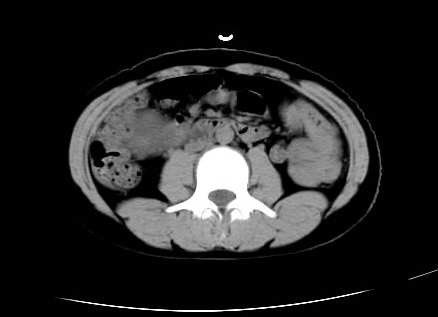

女 16岁  右上腹痛一天,无其他不适

肿块最大径位于十二指肠降段与水平段移行处,并且与肝脏压迹呈“0”形征,可以考虑位于肝外并与胃肠道关系紧密,考虑胃肠道间质瘤(gist)可能较大,须除外神经节起源肿瘤。

肿块与十二指肠关系密切,支持间质瘤诊断.肝脏与结肠均为受压改变.

我坚决反对您的观点,该病例定位:横结肠肝曲与升结肠之间的肠系膜及部分肠壁。请看下图:

病灶巨大,少部分向肠腔内生长,大部分向长腔外生长。其密度不均匀,增强显示明显不均匀强化,并见有大片状始终不强化的不规则坏死液化区。虽然病灶中上部形态尚可,病人又如此年轻,但中下部形态、密度、强化特点强烈提示为恶性病灶。综上,我考虑本病例为:恶性胃肠道间质瘤。